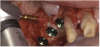

A 72-year-old man was referred for removal of failing maxillary right posterior implants (Figure 19). The treatment plan included removal of three implants with simultaneous bone augmentation and replacement implants for implant-supported fixed bridgework. Implant removal and bone grafting with rhPDGF (Gem 21®, Osteohealth, www.osteohealth.com) and allograft (MinerOss) and xenograft (BioOss®, Geistlick, www.geistlickonline.com) were used along with titanium mesh for space maintenance (Figure 20, Figure 21 and Figure 22). Six months later, mesh removal revealed type I bone allowing for placement of three implants (Figure 23 and Figure 24).

Figure 21  Bone grafting with rhPDGF, allograft, and xenograft.

Figure 21

Figure 22  Titanium mesh fixation.